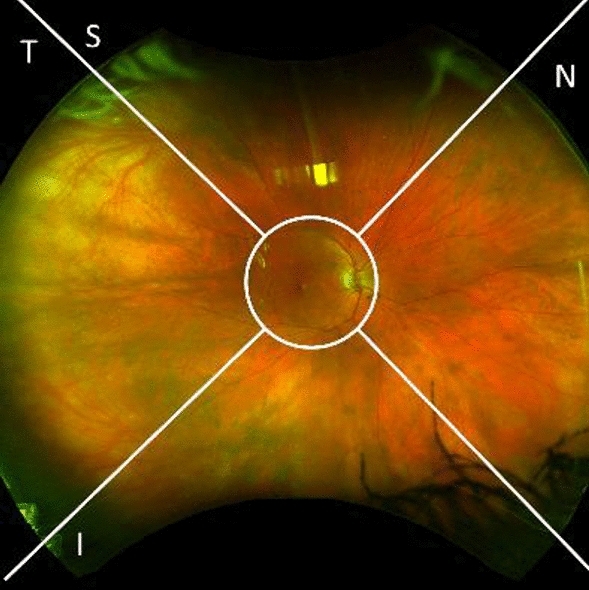

The images were directly and securely downloaded from the OptosAdvance database in JPEG format and processed to exclude the central 45° region of the retina, using previously described methods12. Each remaining 90° section of the images was then divided into four quadrants: superior (S), nasal (N), inferior (I), and temporal (T) as illustrated in Fig. 112. All images were saved in one document using Microsoft PowerPoint (version 16.58, Microsoft Corporation, Redmond WA) and viewed on the same computer screen. Our analysis only relied on pseudocolor images and did not employ the use of red or green filters.

Figure 1.

Quadrants utilized in ultra-widefield pseudocolor image evaluation.